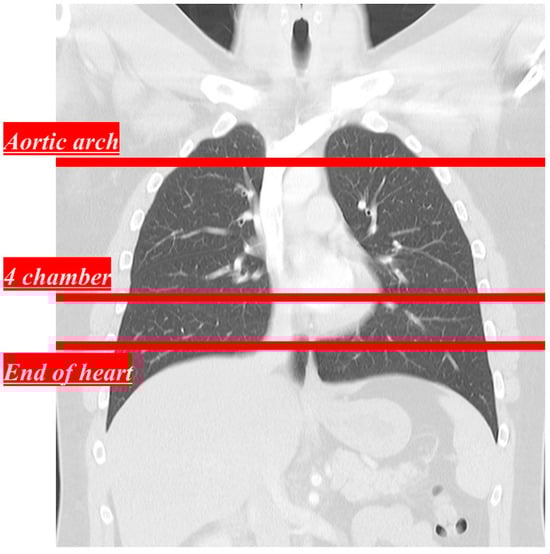

The equipment used in this study was the SOMATOM Force CT imaging system (Siemens Healthineers, Erlangen, Germany). The conditions for obtaining low-dose CT images using a tin filter are presented in Table 1. The parameters of the ADMIRE technique used strengths A2 and A3 as well as kernels B40 and B59. The strengths and kernels used in ADMIRE were the values used in general chest CT scans [19]. The four combinations of ADMIRE parameters used in this study are listed in Table 2. CT images were obtained at three positions: the aortic arch, four chambers, and the end of the heart (Figure 1).

Figure 1. Scan line for each area to acquire CT images: aortic arch, 4 chambers, and end of the heart.